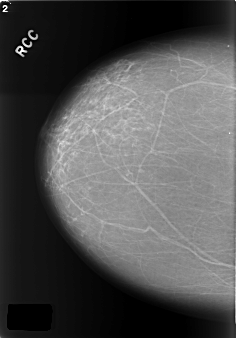

Volume: cancer_09 Case: C-0176-1

C_0176_1.RIGHT_CC

RIGHT_CC LINES 5736 PIXELS_PER_LINE 4024 BITS_PER_PIXEL 12 RESOLUTION 50 NON_OVERLAY